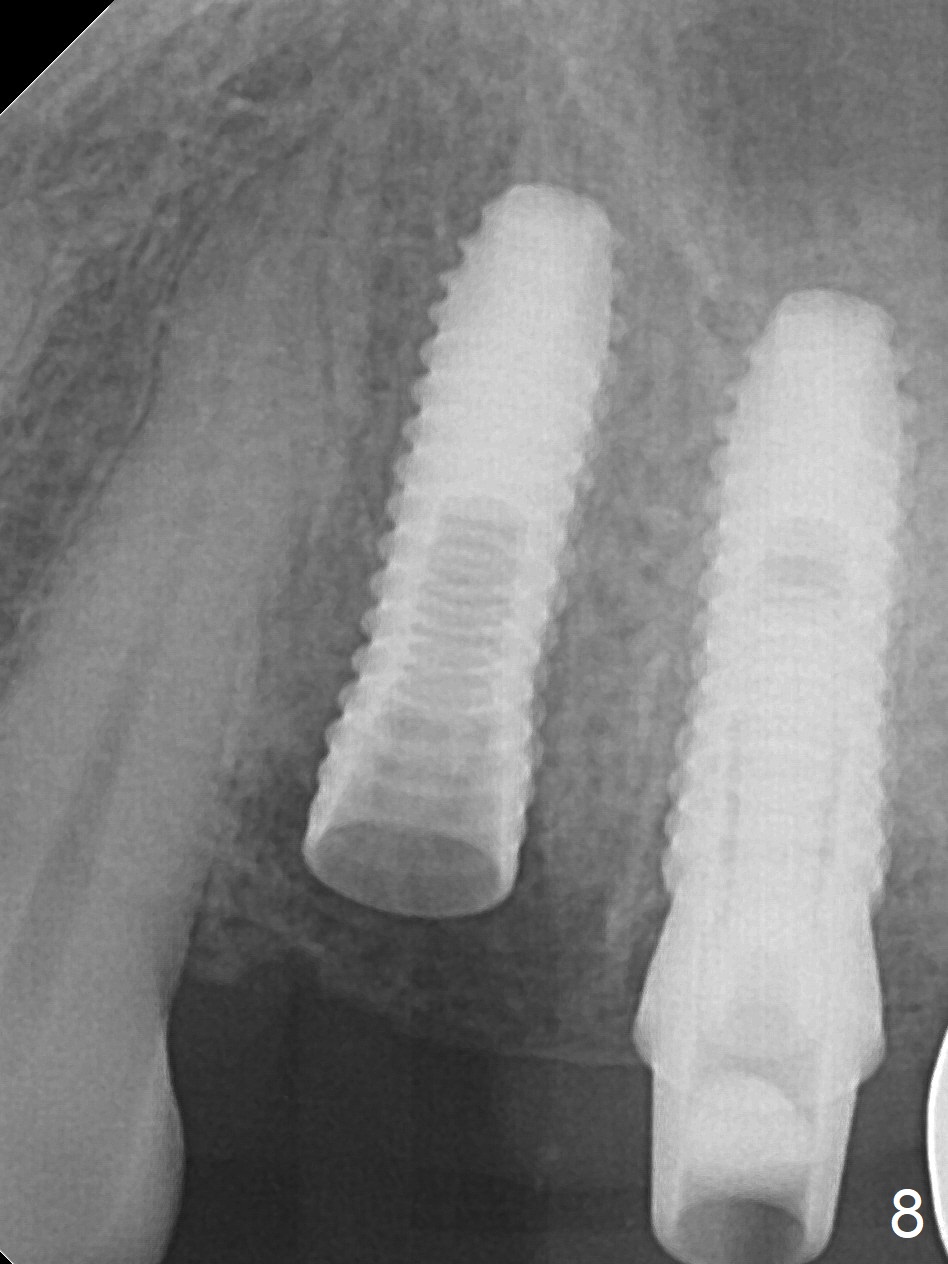

Preop photo shows palatally subgingival fracture (Fig.6). Initial depth is 15 mm at #12 after extraction (Fig.7) and then is extended to 17 mm. In fact the osteotomy is created in the palatal socket, since the septum is thin, while the buccal socket has its apical perforation. A 3.8x13 mm implant is placed (Fig.8); a 4.5x4(3) abutment and allograft are placed (Fig.9 *) prior to immediate provisional fabrication.